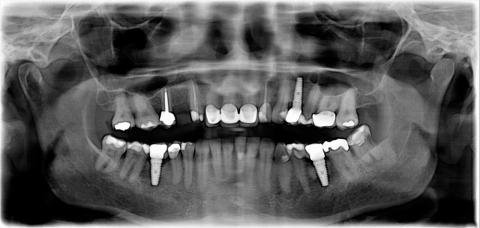

The Panoramic x-ray, is a two-dimensional (2-D) dental x-ray examination that captures all completely the mouth in a single image this are the following the teeth, upper and lower jaws, surrounding structures and tissues.